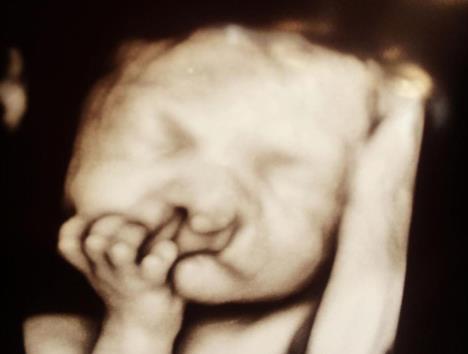

Ultrazvuk je pokazao da će dečak biti rođen s rascepom usne i nepca zbog čega će imati i brojne druge zdravstvene probleme, pa su joj savetovali da ipak izvrši abortus.

316519-ultrazvuk-ff.jpg

Foto: Instagram Printscreen